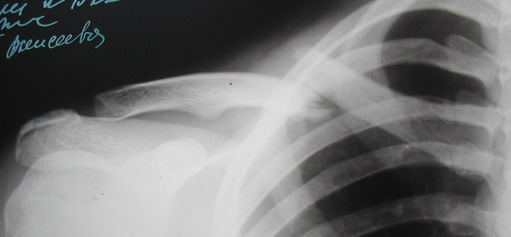

Во время стажировки в Австрии не мог не поинтересоавться, как австрийские хирурги лечат переломы ключицы. Оказалось, при переломах без смещения или с небольшим смещением накладывают восьмиобразную повязку, в остальных случаях выполняют остеосинтез пластинами.